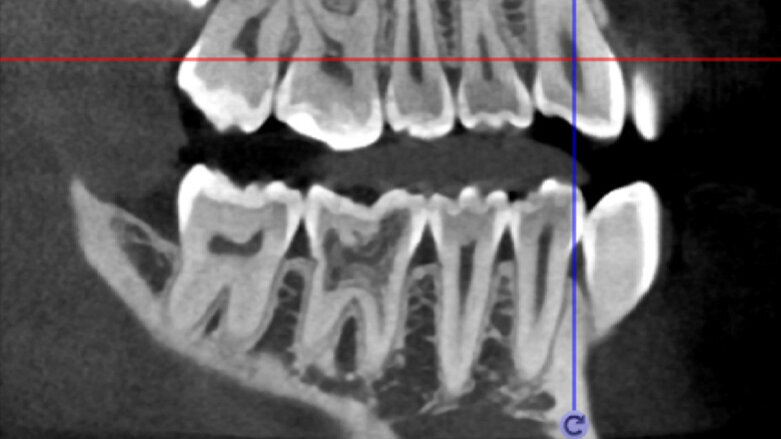

Klinický případ, kterým dále uvádím, je skvělým příkladem toho, jak obtížné je určit původ pacientových symptomů pouze na základě intraorálního snímku. Vizualizace 2D snímku selhává v jistotě určení přítomnosti léze, ještě důležitější však je, že je nemožné určit velikost, morfologii a typ léze, kterou se podaří nalézt. Analýza 3D snímku nám poskytne jasnou představu o klinické situaci: koronální a sagitální řezy odhalily přítomnost veliké léze sahající od apexu meziálního kořene tohoto moláru do furkace, zatímco axiální řezy nám umožňují provést přesnou analýzu endodontické anatomie a obzvláště pak tvaru meziálního kořene, který byl v tomto případě spojen s palatinálním kořenem. Celkový přehled o situaci ovlivňuje rozhodování o postupu a stanovení léčebného plánu zahrnujícího speciální úkony (obr. 1–4).